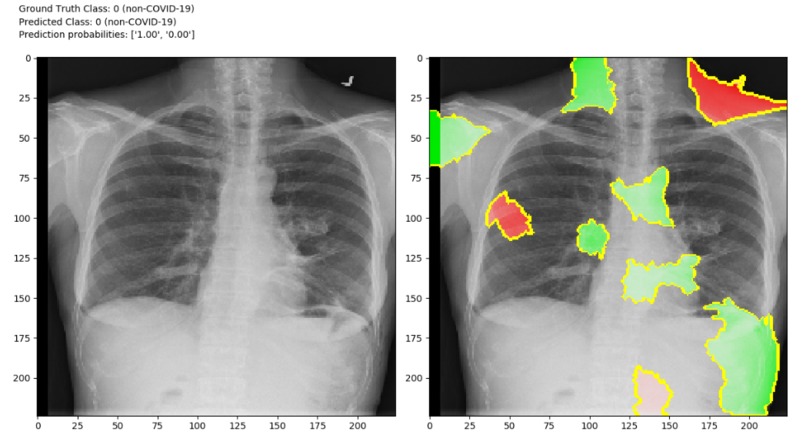

Although there is one drawback that X-ray analysis requires a radiology expert and takes significant time. Which is precious when people are sick around the world. Therefore, developing an automated analysis system is requires to save medical professionals valuable time.we can identify the difference in those two images. So, we can create a software which can identify difference between those two images using image processing techniques and Artificial Intelligence. We can Train AI model with features of normal person’s X-ray data and COVID19 patient’s X-Ray image data.

Detection of COVID19 symptoms is not only essential but also difficult task as it is current pandemic. COVID19 affects the lungs so if we detect in few seconds it will save doctors and health workers valuable time.

The primary objective is to develop the automated system that will detect the symptoms of COVID19 using X-Ray image.The secondary objective is to identify case of COVID19 positive or negative. Our goal is to use X-ray or CT images to develop AI based approaches to predict and understand the infection. We will release these models using our open source Chester AI Radiology Assistant platform which is designed to scale to a global need by performing the computation locally.